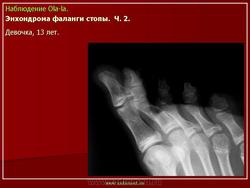

Энхондрома фаланги.

Источником роста хондромы могут явиться нормально расположенный хрящ (суставной, ростковый) и участки дистопированного хряща, а также очаги неокостеневшего эмбрионального хряща. Наиболее часто хондромы встречаются у детей в возрасте 11 -16 лет. Как и все первично-доброкачественные новообразования, хондрома характеризуется солитарным очагом в одной кости. Множественные хондромы, как правило, вторичны и сопровождают диспластический процесс.